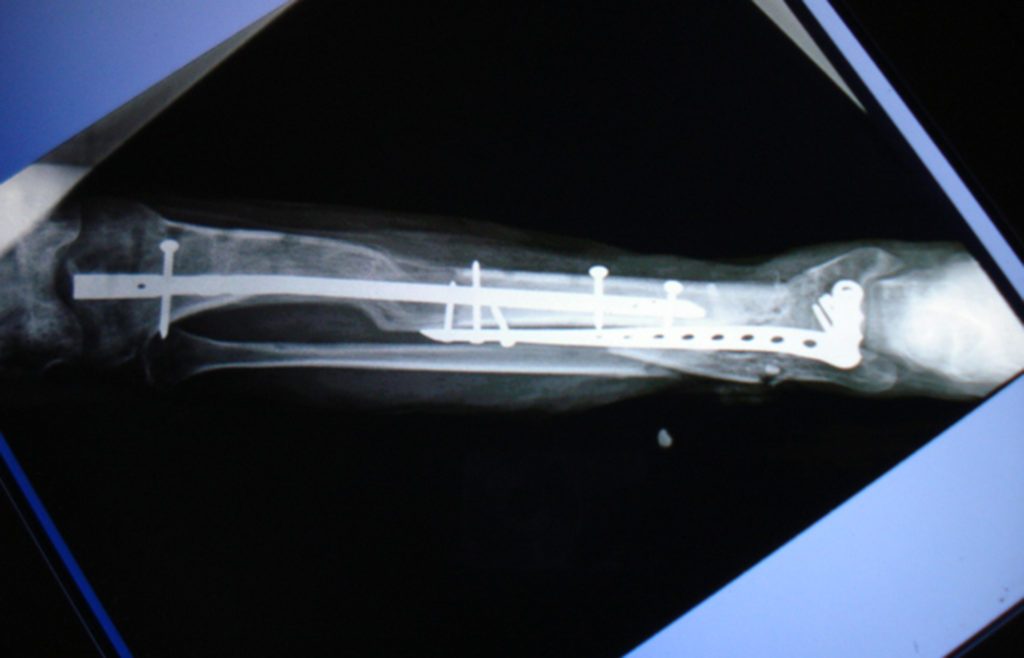

La doctora Fryda Medina Rodríguez, Directora General de la UMAE y quien encabeza el equipo de cirugía, explicó que esta técnica consiste en varios procedimientos: primero se retira el tejido muscular muerto, después se coloca una barra y un tornillo -que permanecen fijos a la extremidad-, y se realiza una incisión en la parte superior del hueso.

Posteriormente se coloca una esponja que ayuda a la regeneración de los tejidos. El aditamento empuja la masa muscular sin obstruir los vasos sanguíneos, y se cubre con piel el tejido expuesto.

Explicó que la elongación ósea permite que el hueso se alargue un milímetro por día, al hacer girar el tornillo 45 grados cada seis horas, día y noche; acción que el paciente debe realizar una vez que es dado de alta del hospital.